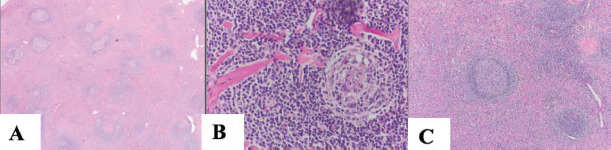

Results: Our review identified 35 documented cases of intrapulmonary UCD, including our case. The average age was 34 years, with a female predominance of 57.7%. Tumor sizes ranged from 1.5 to 11 cm, with our case being the largest. Of the 24 cases with reported anamnesis, 58.3% were asymptomatic, while 41.7% had nonspecific symptoms such as cough, chest pain, or fever (as in our case). Histological analysis was available for 24 cases, with 83.3% identified as the hyaline vascular type. Biopsies through small needle aspiration or fresh-frozen samples failed in all attempts, requiring resection for diagnosis and treatment. Due to high vascularity, delicate location, and lack of diagnosis, lobectomy or pneumonectomy was performed in 45.7% of cases. Among the 11 cases with reported follow-up, no disease recurrence was observed over an average of 3 years.

Abstract Image